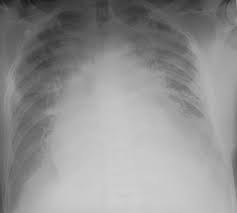

Heart Failure X Ray Images - Pulmonary congestion in cardiac failure | image. Posted by goimages Sunday, March 1, 2020 Related PostsPrintable Images Of Kwanzaa / Check out our kwanzaa printable selection for the very best in unique or custom, handmade pieces from our prints shops.Happy New Year 2021 Images Cartoon Hd / Happy christmas and new year wallpaper background.Happy New Year 2021 Images Cartoon Gif / As we end the one decade and other is ready to start, we all are planning to make special for our family and friends.Happy New Year 2021 Best Cartoon Images / Share the best gifs now >>>. Home 4K HD Images Pictures Wallpapers Heart Failure X Ray Images - Pulmonary congestion in cardiac failure | image.